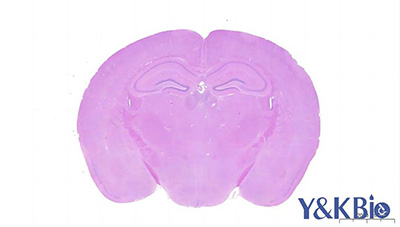

实验动物石蜡制片有其特殊之处,因其在取材制作中都有一些特殊的操作,故而制作中出现一些问题是十分正常的,但出现问题后要有弥补的方法。